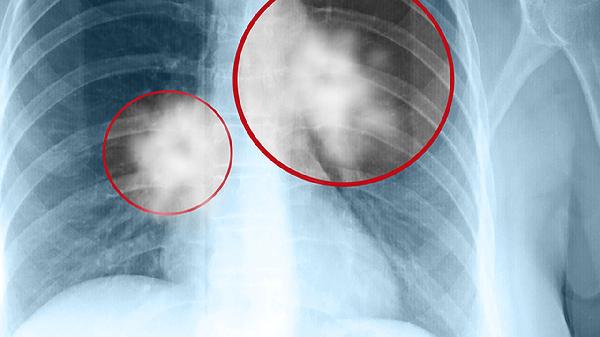

左肺少许炎症左下胸膜增厚粘连是影像学描述,提示左肺局部轻度感染及胸膜反应性改变,可能与肺炎、结核或既往胸膜炎有关。

左肺少许炎症通常指肺部局部存在感染或非感染性炎性反应,影像学表现为肺组织密度增高或模糊影。常见于细菌性肺炎、支原体肺炎等,患者可能出现咳嗽、咳痰或低热症状。胸膜增厚粘连多因胸膜腔炎症后纤维蛋白沉积导致,常见于结核性胸膜炎、细菌性胸膜炎或外伤后,表现为胸膜层增厚、分层不清,可能伴随胸痛或呼吸受限。这类改变需结合临床症状判断,若为陈旧性病变且无症状可观察,活动性感染需抗感染治疗。

胸膜粘连严重时可能影响肺扩张功能,导致限制性通气障碍。少数情况下需考虑恶性肿瘤胸膜转移或自身免疫性疾病如类风湿性胸膜炎,这类情况多伴随体重下降、持续胸痛等全身症状。影像学动态随访对鉴别诊断尤为重要,必要时需进行胸腔镜活检明确病因。